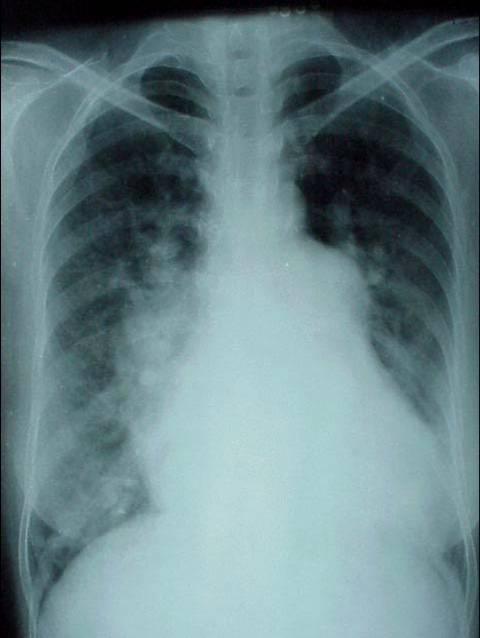

照片名称:肺转移瘤